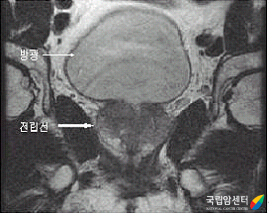

전립선암의 MRI 소견

2009.08.24